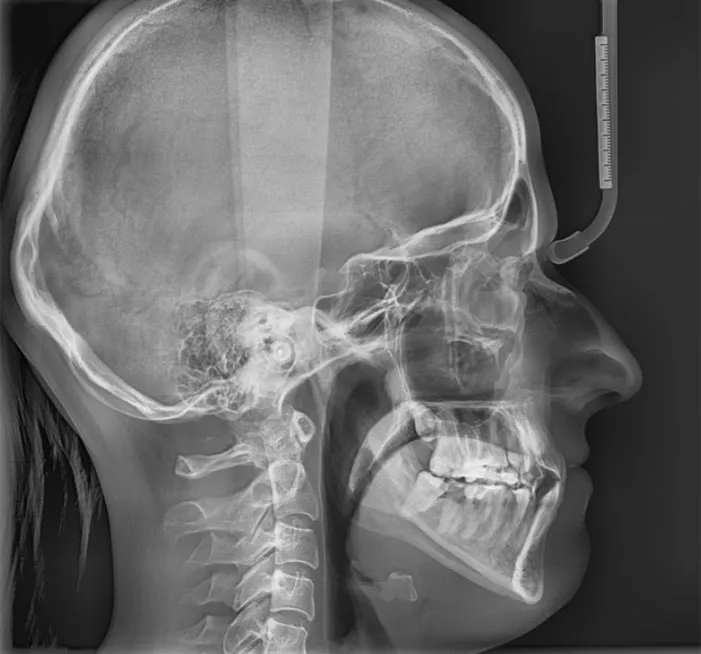

Aby ortodonta mógł postawić trafną diagnozę i zaplanować skuteczne leczenie, niezbędne są badania diagnostyczne. Obejmują one zazwyczaj zdjęcia rentgenowskie (pantomograficzne i cefalometryczne) oraz wyciski lub skany 3D szczęki i żuchwy. Łączny koszt tych badań to dodatkowe 250-500 zł. To inwestycja, której nie można pominąć, ponieważ stanowi fundament całego procesu.